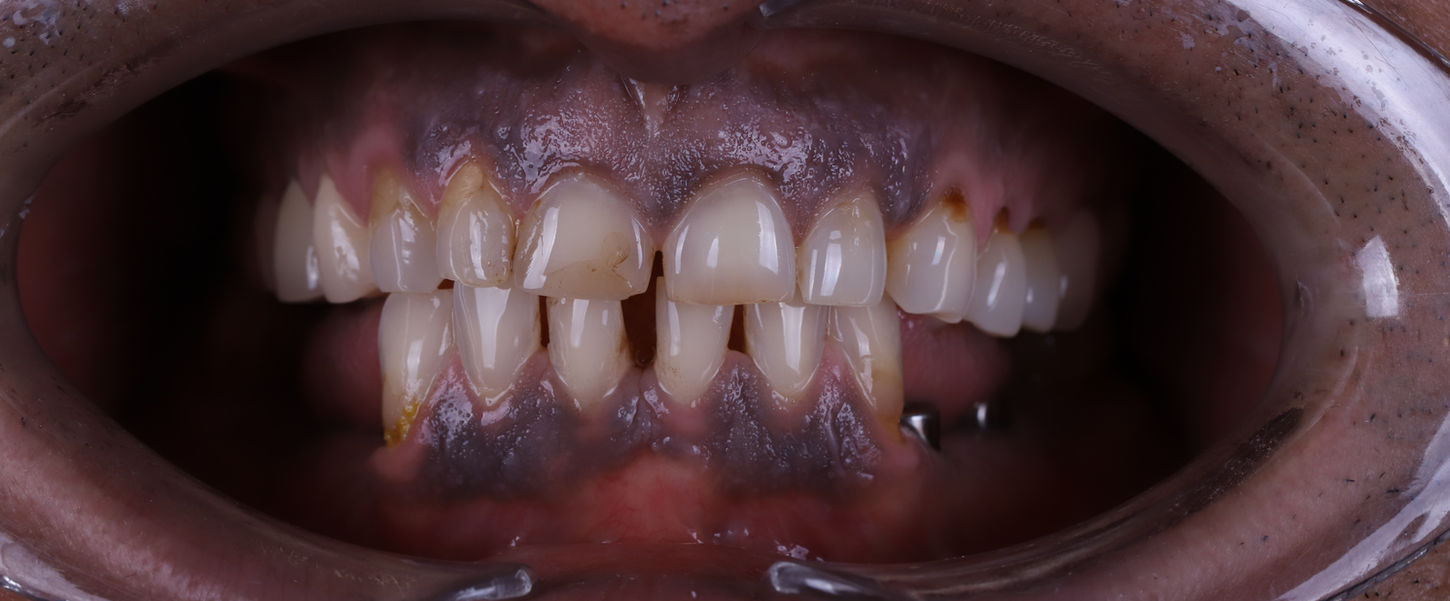

Gülüş Tasarımı

Fotoğraflar